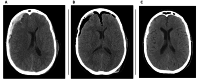

Figure 2. Preoperative and postoperative computed tomography scans of the same patient with subdural hematoma

(A) Axial view of a computed tomography (CT) scan depicting an acute subdural hematoma of a patient from our series. (B) Axial view of a CT scan of the same patient in the immediate postoperative phase. (C) Axial view of a CT scan of the same patient during a follow-up visit four weeks after surgery.